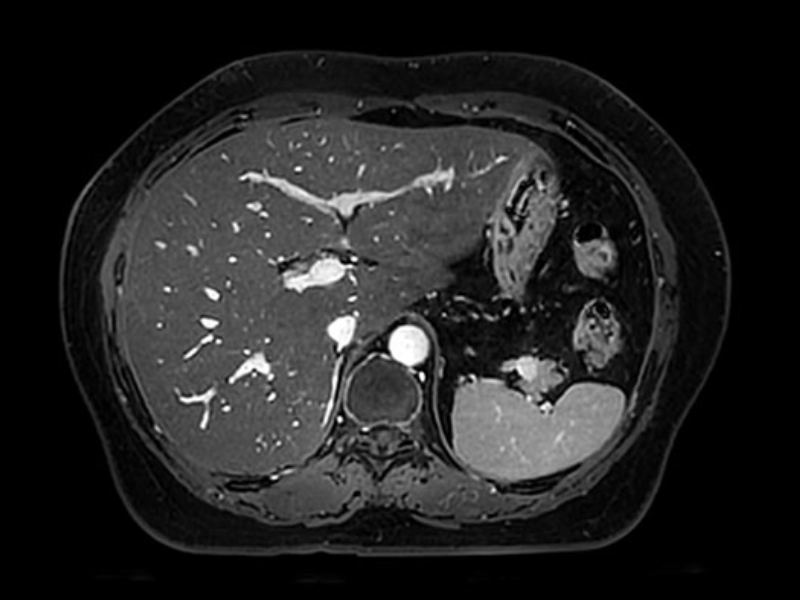

Axial CE T1 of the abdomen